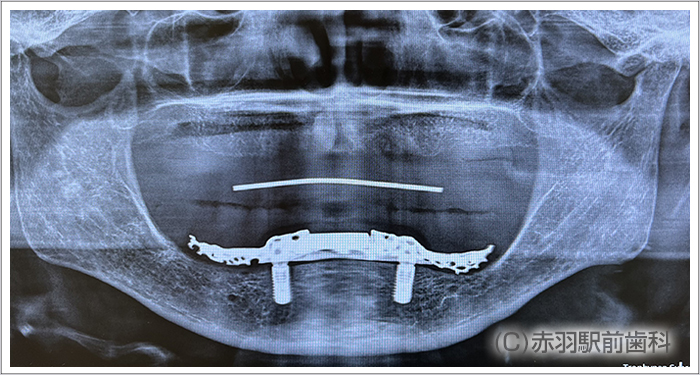

CTデータから事前に3Dプリンターで、患者様の実寸代の顎骨模型を作成しておいて手術前にシミュレーションで担当医がインプラント埋入とSRAアバットを装着しておきました。画像は下顎の模型です。両サイドのインプラントはオールオン4特有の傾斜埋入をしてあります。

シミュレーション通りの位置にインプラント手術を完了しました。上下ともに両サイドのインプラントはオールオン4特有の傾斜埋入をしています。